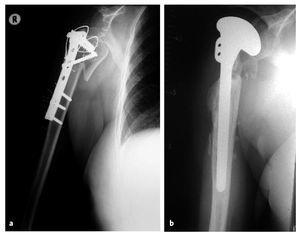

Figuras 10a y 10b. a) Mujer de 63 años con placa de osteosÃntesis en el húmero proximal para fijar una fractura conminuta colocada en otro centro en agosto de 2002. b) Revisión a hemiartroplastia (Neer II) en septiembre de 2002 en otro hospital para resolver una luxación de la placa y malalineación persistente de los fragmentos de la fractura. El paciente se presentó en nuestras consultas externas en septiembre de 2003. La puntuación de la Escala de Constant era de 16 con dolor y limitación de la movilidad (flexión 70º, abducción 70º). La hemiartroplastia habrÃa migrado anterosuperiormente debido a la insuficiencia del manguito de los rotadores. El paciente fue ingresado para cirugÃa de revisión protésica del hombro.

Figuras 11a y 11b. RadiografÃas del hombro derecho (a: AP, b: proyección axial) 25 meses tras la cirugÃa. Se colocó una prótesis invertida de vástago largo. Ventana ósea quirúrgica fijada con un cerclaje alámbrico.

Figuras 12a a 12d. Movilidad a los 25 meses de la operación. Flexión activa 140º y abducción 100º. Existe un déficit residual evidente en la rotación externa activa con el brazo en abducción. La puntuación del Constant mejoró hasta 58,6 puntos (83,7% ponderado por edad). La paciente no tenÃa dolor y estaba muy satisfecha con el resultado quirúrgico.